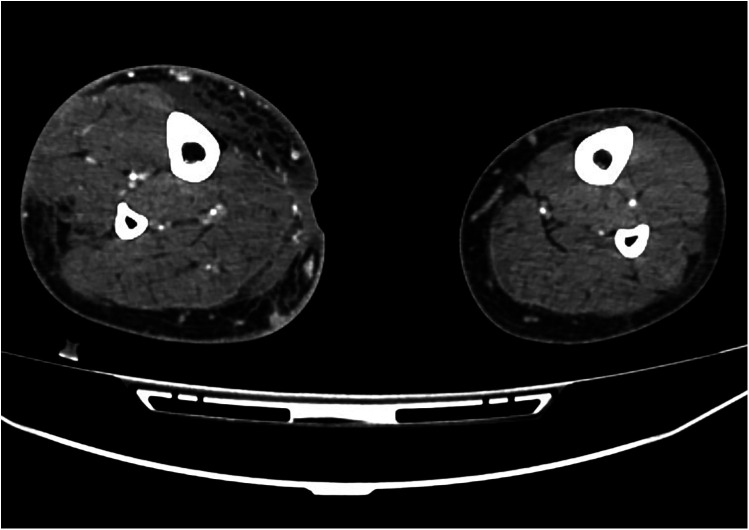

经动脉微栓塞(TAME)已被公认为慢性肌肉骨骼疼痛的微创治疗方法,具有显著的疗效和良好的安全性(1,2)。然而,并发症的报道仍然不足。本病例报告描述了第一个记录严重不良事件的患者慢性静脉溃疡接受TAME微动静脉瘘(AVF)。患者出现了明显的并发症,包括广泛的腿部肿胀、皮肤变化和蜂窝织炎,需要长期住院治疗。这些发现强调了患者选择和栓塞剂考虑的重要性,以减轻与TAME相关的潜在风险。

Transarterial microembolization (TAME) has gained recognition as a minimally invasive treatment for chronic musculoskeletal pain, demonstrating significant efficacy with a favorable safety profile ( 1, 2). However, complications remain underreported. This case report describes the first documented severe adverse event in a patient with a chronic venous ulcer undergoing TAME for a micro arteriovenous fistula (AVF). The patient developed significant complications, including extensive leg swelling, skin changes, and cellulitis requiring prolonged inpatient care. These findings highlight the importance of patient selection and embolic agent considerations to mitigate potential risks associated with TAME.